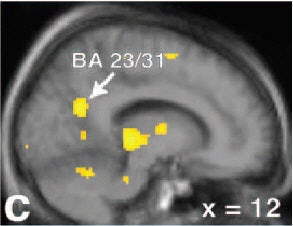

| Left, coronal image (d) showing greater bilateral amygdala activations for males versus females for the couples versus neutral stimuli contrast within those regions showing greater activity for males versus females. Couples versus neutral stimuli contrast for males (e), at the same coronal and axial views. The same contrast and views for females (f), showing an absence of differential activity in the ROIs. Figure 2 from Nature Neuroscience, Vol.7, pp. 411 to 416, "Men and women differ in amygdala response to visual sexual stimuli" by Stephan Hamann, Rebecca A Herman, Carla L Nolan, Kim Wallen , et al. |

"Notably, in no region did females show significantly greater activation than males...the greater amygdala activation in males observed here may in part reflect a greater appetitive incentive value of visual sexual stimuli...," Hamann and colleagues noted.